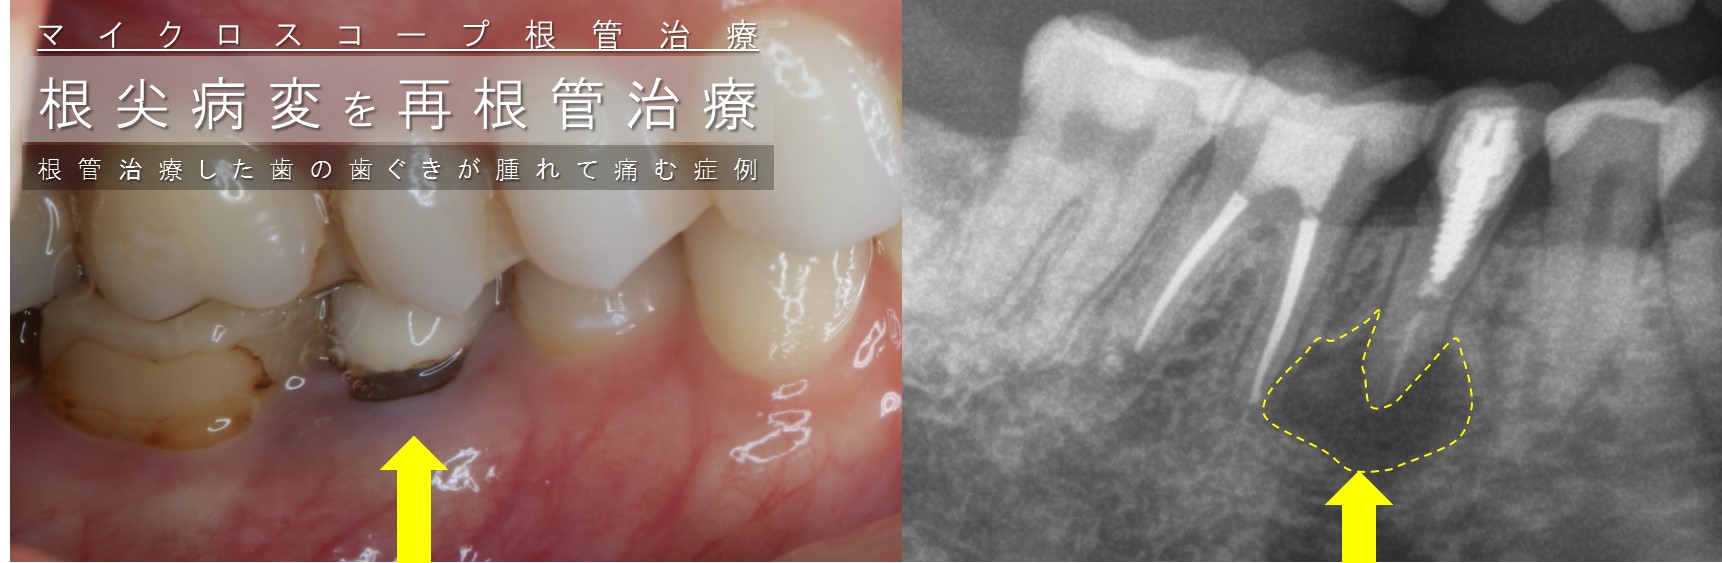

再根管治療 根っこ 神経 歯ぐきが腫れた 根尖病変ある 治したい 都内港区新橋霞が関虎ノ門日比谷千代田区歯科歯医者 術前術後

根尖病巣 根尖病変 そのままでいいの